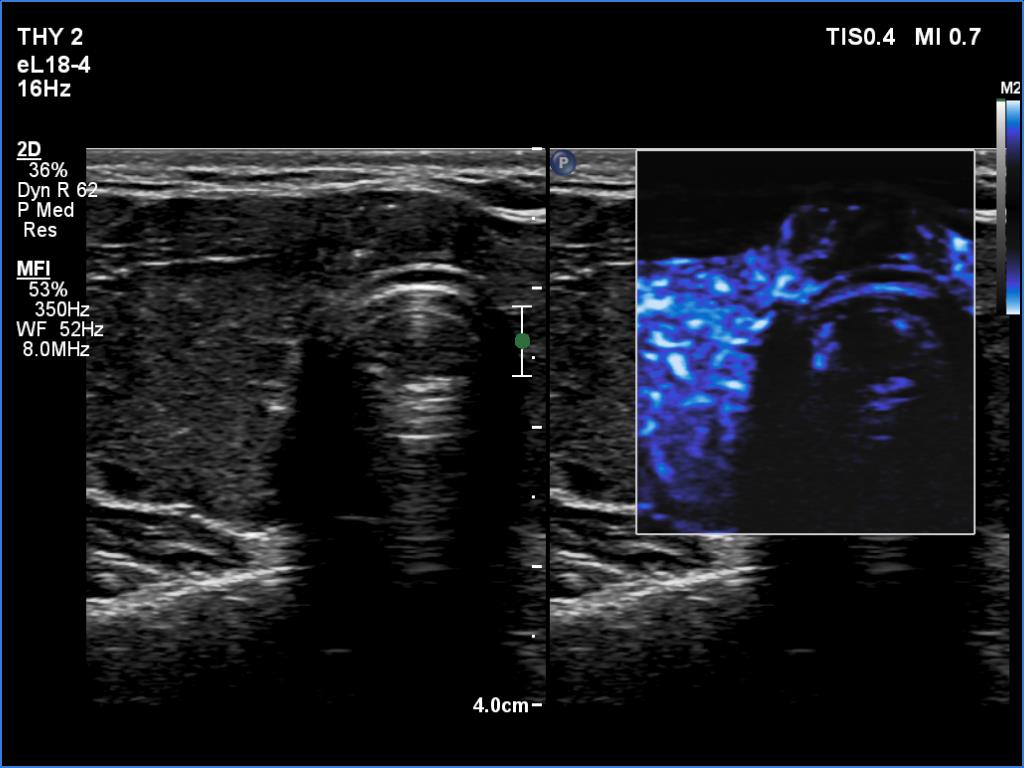

Right lobe, longitudinal scan

Isthmus, transverse scan, microflow imaging. Compared with the extranodular tissue, the vascularity is strikingly lower within the tumor.